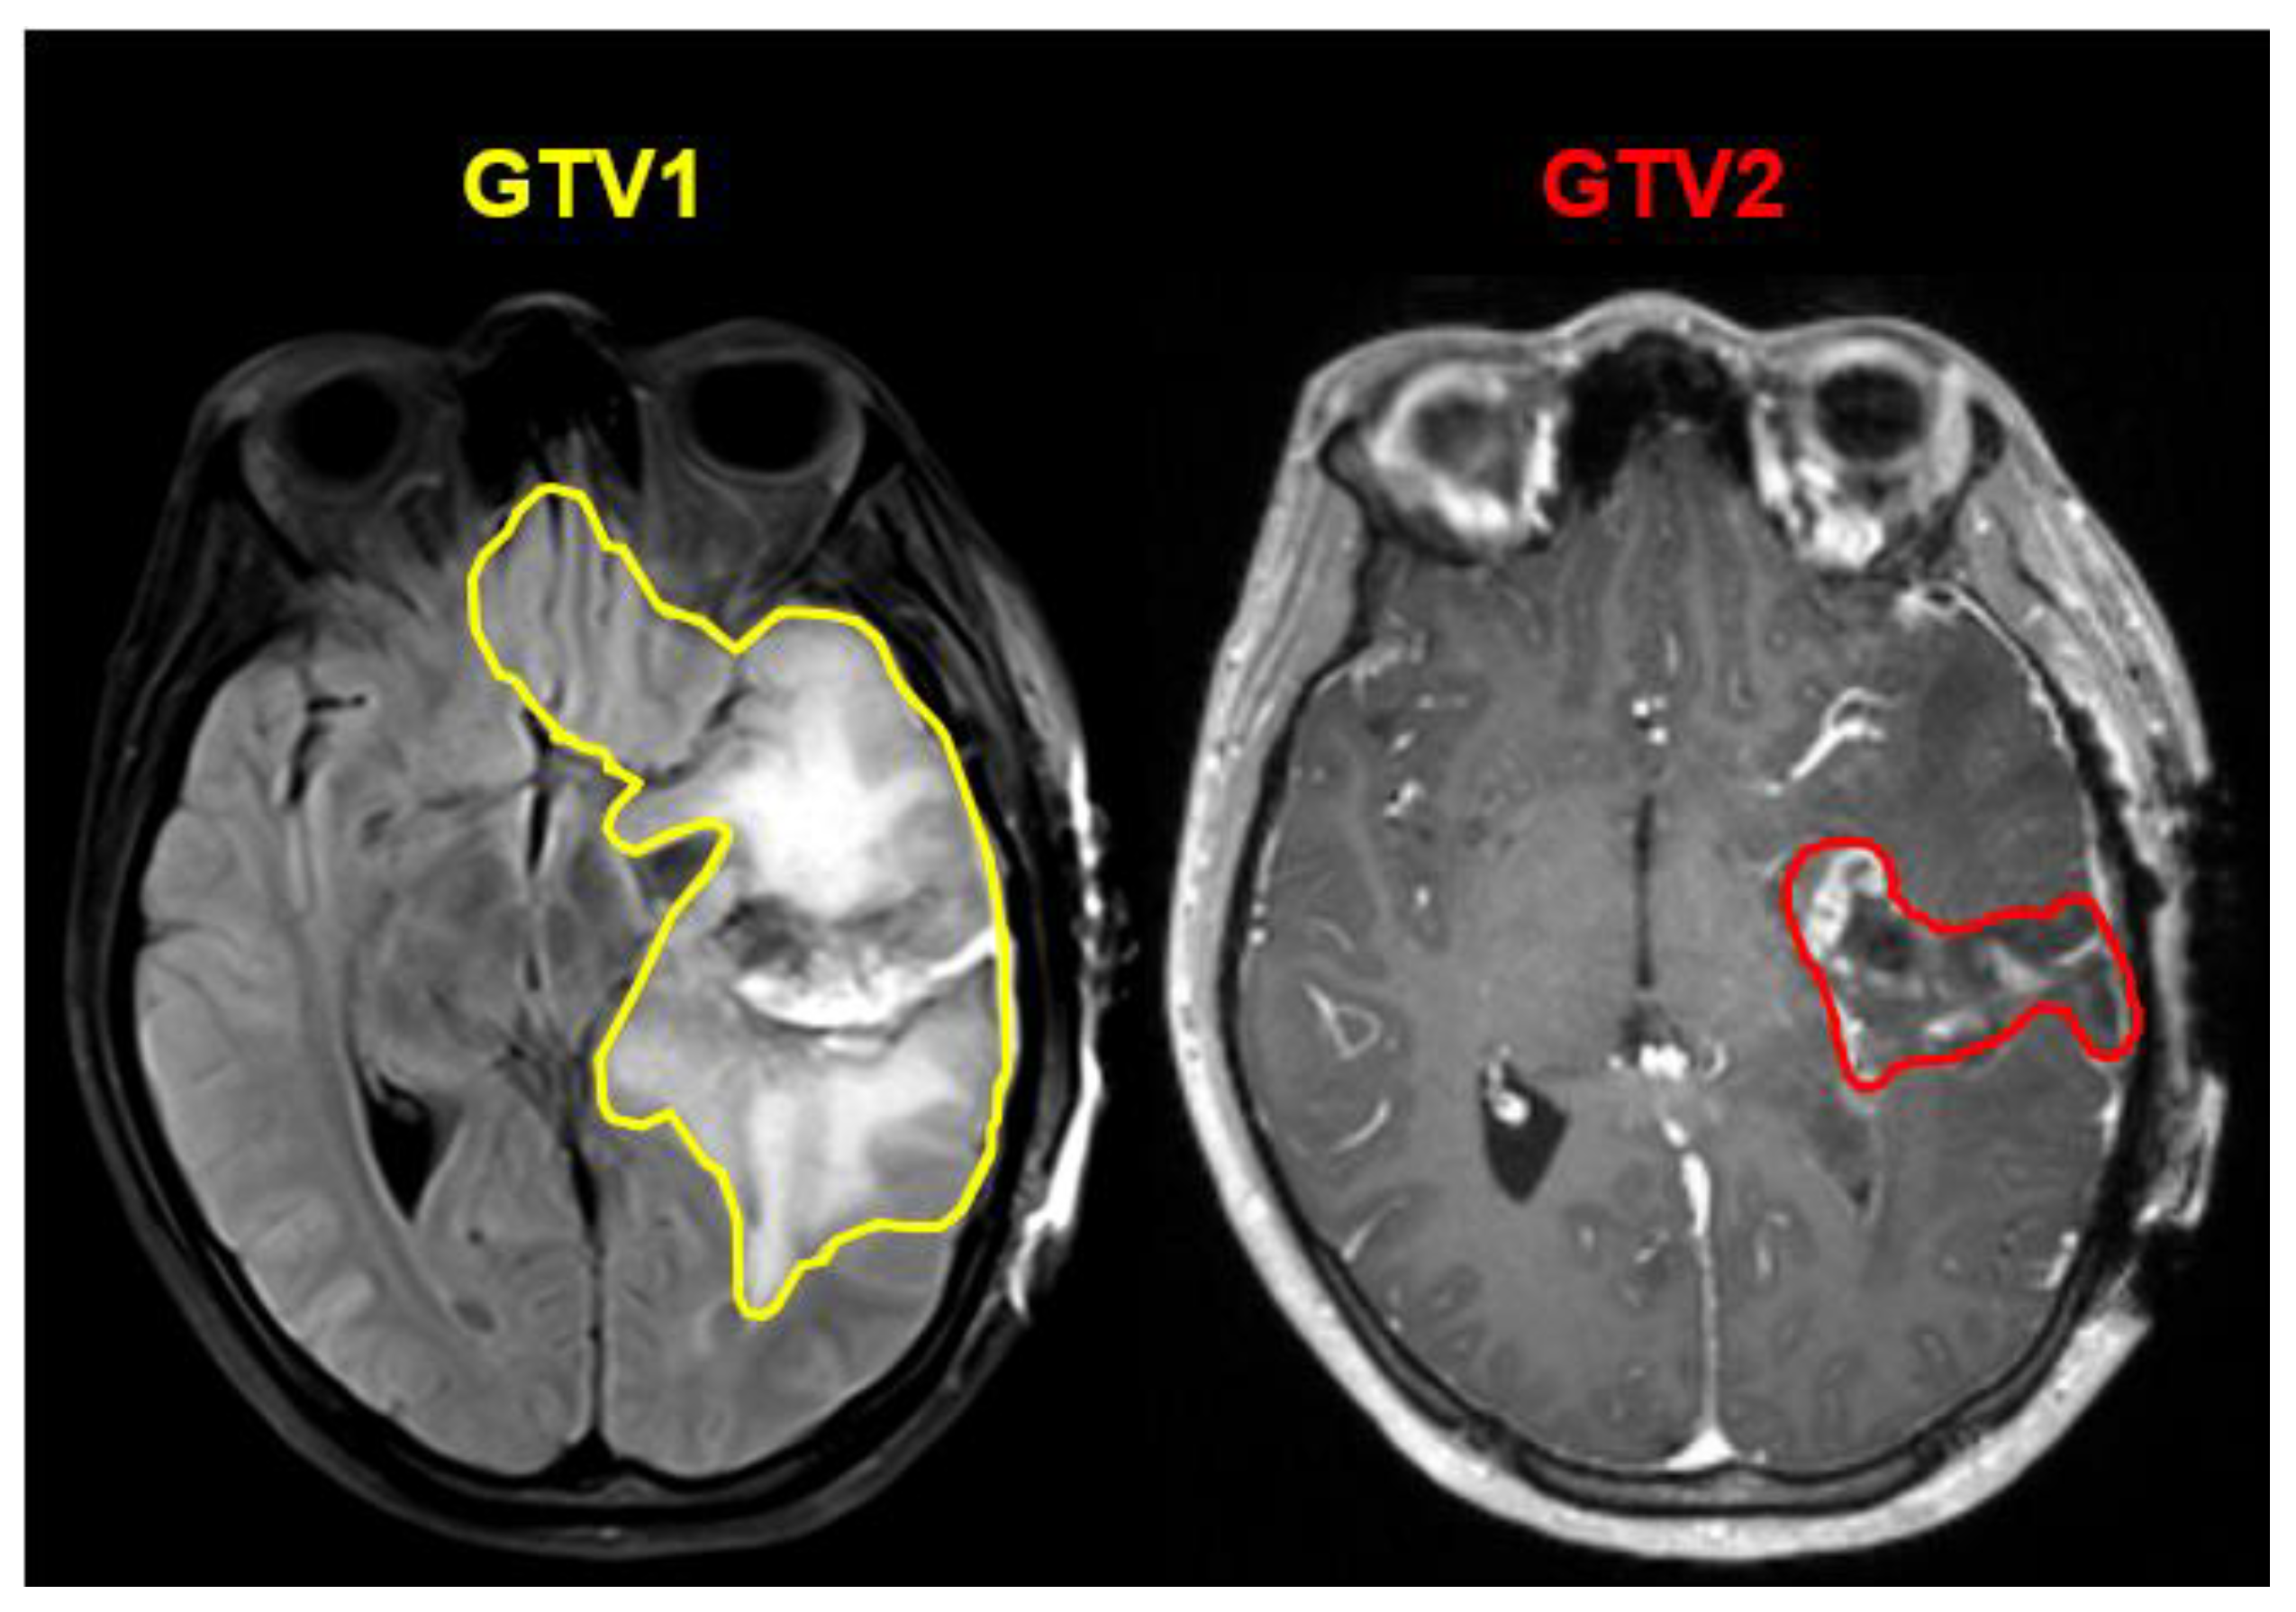

2.1. Preparation of Training Data

3.1. Segmentation for RT Planning